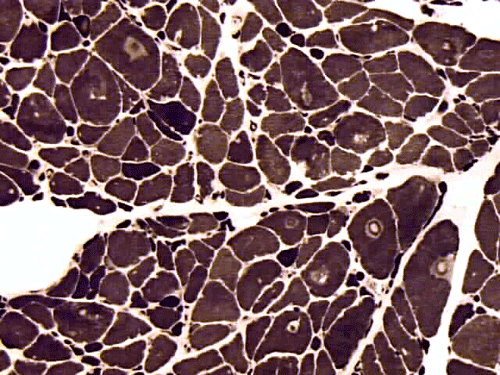

On hematoxylin-eosin stained sections, there is an increased variation of fiber diameter with many atrophic fibers intermingled with fibers of normal caliber. There is no evidence of fiber grouping or perifascicular atrophy. No inflammatory cells are present. There is also mild interstitial fibrosis (Panel A). On higher magnification, many fibers have a round concentric structure (Panel B). Irregular, centrally located depositions are also identified on modified Gomori's trichrome. The concentric nature, however, is not as obvious as in the hematoxin-eosin stained sections (Panel C). Type I and II fibers are not clearly separated in the ATPase preparation at pH 9.4. This is a common situation in chronically ill muscle (Panel D). The type I fibers are unusually dark. There is an increase in the proportion of type I fibers. The atrophic fibers are usually type II fibers. The concentric lesions are found predominantly in type I fibers (Panel E). There is an increase in PAS staining which is consistent with increased glycogen storage (Panel F). No increase in lipid content is demonstrated by oil red O (Panel G). On NADH-TR reaction, the concentric structures appear to have a clear central core that is devoid of enzymatic activity, a rim with intense enzymatic activity and a surround zone with relatively normal reactivity. These features are classic for target fibers (Panel H and I). No deficiency of laminin-2 (merosin) (Panel J) or dystrophin (Panel K) is demonstrated by immunohistochemistry. The central lesions are also immunoreactive for both laminin-2 and dystrophin. Immunohistochemistry for desmin demonstrate a core of strong immunoreactivity and also strong reaction in the sarcoplasmic membrane (Panel L and M). The target structures are also well demonstrated on semithin sections (Panel N). On electron microscopy, z-disc streaming is a common finding and they are often admixed with a substantial amount of dense granular electron dense substance (Panel O and P). There are also numerous cytoplasmic bodies characterized by radiating intermediate filaments (spheroid bodies) (Panel Q and R).

Pathology

The two major pathologic findings are inclusion bodies and granulofilamentous material. Type I fibers are predominantly affected. Inclusions are eosinophilic on hematoxylin-eosin stain and bluish on modified Gomori’s trichrome stain. These inclusions are often negative for oxidative enzymes. A strong reactivity for desmin can be demonstrated by immunohistochemistry. The abnormal accumulation can occur as cytoplasmic inclusions, subsarcolemmal inclusions, spheroid bodies (10-20 mm oval or spherical inclusions), and patches or “hyaline structures”. In some cases, there is Z-disc streaming but no masses are demonstrated by trichrome stain. Numerous negative areas may be demonstrated by oxidative enzyme reactions. An accentuated intermyofibrillar network is seen by antidesmin antibody staining. Under the electron microscope, spheroid bodies appear as cytoplasmic bodies with a dense, granular core surrounded by fine filaments in a coronary arrangement. Although they are conspicuous on light microscopy, they may not be as distinctive at the ultrastructural level.